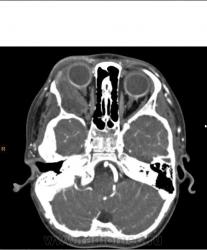

Эхинококкоз орбиты

Мальчик, 5 лет. Случай верифицирован (операция, гистология).

Да, экзофтальм - основная жалоба.